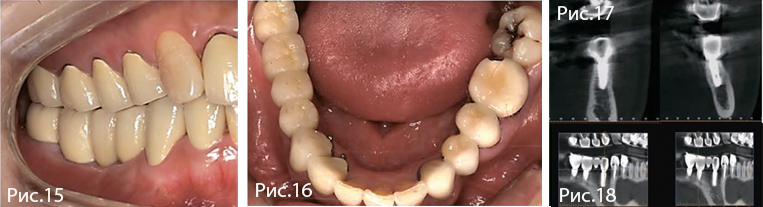

Рис. 15—18. Окончательное протезирование через 14 недель после имплантации. Ширина гребня и объем кератинизированной десны стабильны. На КТ отмечают оптимальную костную поддержку имплантатов в области первого премоляра и первого моляра.